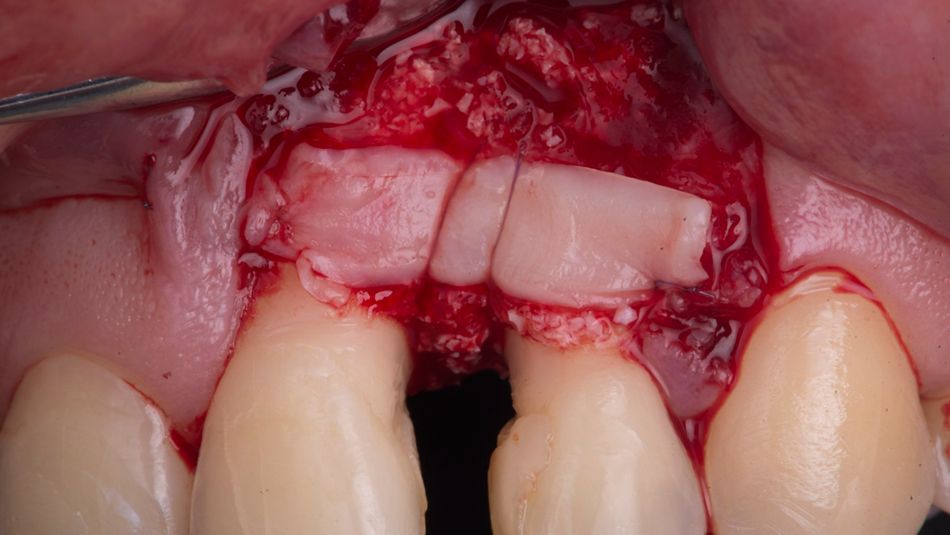

Meticulous scaling and root planing was performed (Fig. 4) and revealed a combined 1- and 2-wall osseous defect (Fig. 5).